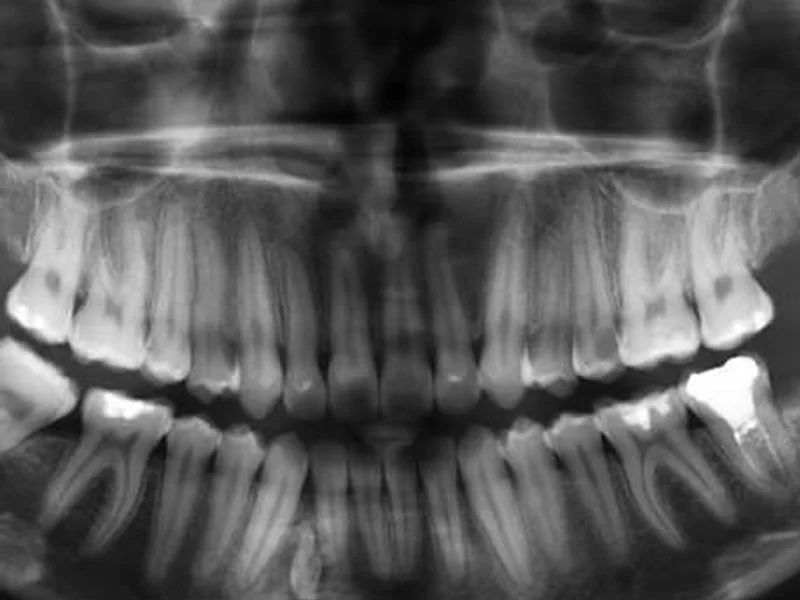

Snimanje digitalnih ortopana, pojedinačnih zuba, sinusa i temporomandibularnog zgloba u Vukovaru.

- –Ortopan

- –Ortopan 1:1

Ortopan

25 € po jedinici

Ortopan 1:1